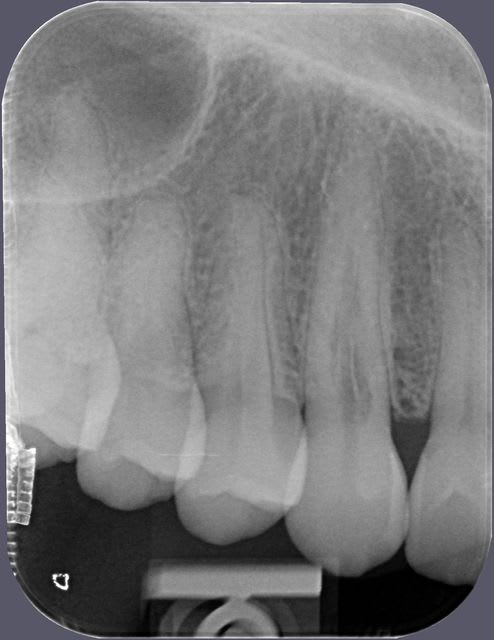

patiente 37 ans

dent asympomatique

radio 2011 et 2012

La résorption interne est un processus consécutif à une inflammation du nerf.

Ce phénomène est évolutif, donc il faut intervenir : traitement endo avec inter séance d'hydroxyde de calcium.